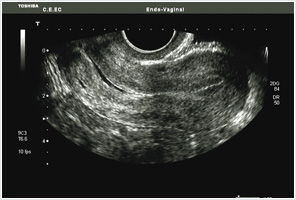

Efectuada com sonda abdominal, complementada com sonda vaginal, permite a observação dos órgãos pélvicos, nomeadamente do útero e dos ovários, e detectar eventual patologia.

Ecografia ginecológica de rotina

Permite detectar eventuais alterações sem que haja suspeita clínica.

Ecografia ginecológica para esclarecimento diagnóstico

Esta técnica é um importante contributo para o esclarecimento de suspeitas ou diagnósticos clínicos de doenças ginecológicas.